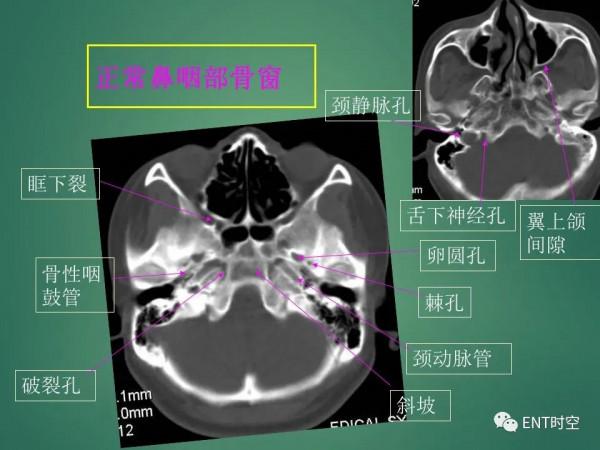

高畫質鼻咽部CT解剖